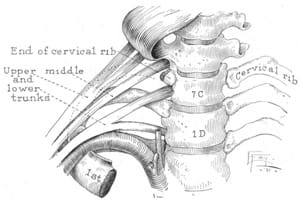

A cervical rib is an extra rib in the lower neck, above the normal first rib. Overall, cervical ribs are seen in about 0.5 to 1% of the human population. In detail, a cervical rib may be unilateral or bilateral, small or large, free-floating or fused to the first rib on the same side. While many physicians associate cervical ribs with thoracic outlet syndrome, the presence of a cervical rib does not prove or disprove thoracic outlet syndrome. Demonstration of cervical ribs goes back centuries, but association with TOS was only demonstrated in the early 19th century.

Gruber published a classification system for cervical ribs. His classification was based on the length of the cervical rib and its attachment to the first rib.

Type 1: Cervical rib extends to the transverse process of C7

Type 2: Cervical rib extends beyond the transverse process with no connection to the first thoracic rib

Type 3: Cervical rib extends beyond the transverse process with partial fusion to the first rib by fibrous bands or cartilage

Type 4: Cervical rib is completely fused to the first rib by a bony pseudoarticulation